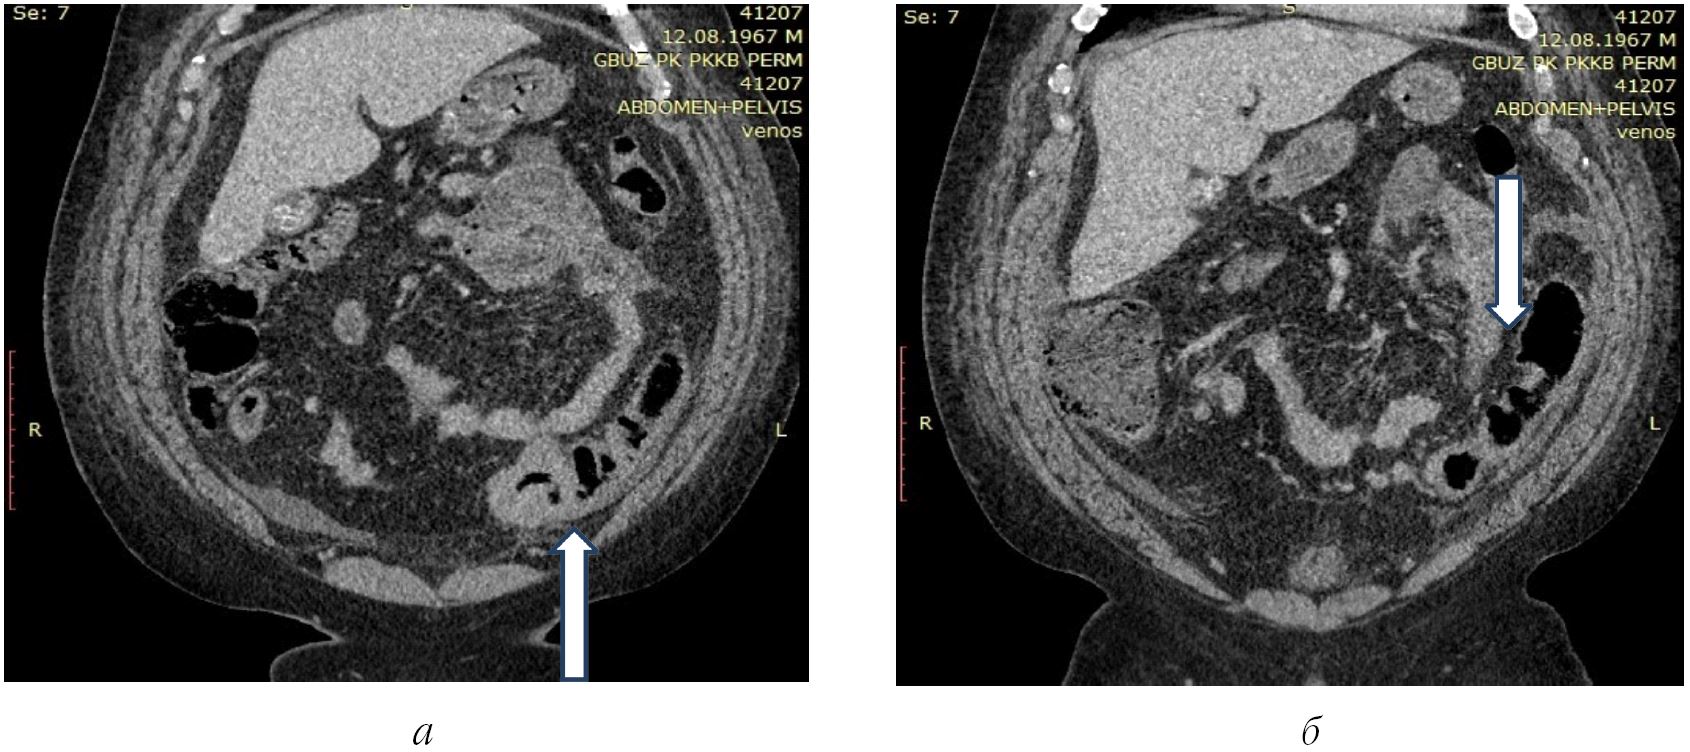

Пациент К., 54 года, поступил в экстренном порядке 13.11.2021 в приемное отделение Пермской краевой клинической больницы с жалобами на постоянную ноющую боль в обеих подвздошных областях, тошноту, одышку. Заболел остро за 3 ч до поступления. При осмотре состояние средней тяжести. Пациент с морбидным ожирением, рост – 175 см, вес – 148 кг, индекс массы тела 48,9. В сознании, адекватен. Температура тела нормальная. Частота дыхательных движений – 22 в мин, частота сердечных сокращений – 84 в мин, артериальное давление (АД) – 150/90 мм рт. ст., SpO2 – 98 %. Живот значительно увеличен в размерах за счет избыточной подкожно-жировой клетчатки. Перистальтика выслушивается. Симптом Щеткина – Блюмберга положительный в обеих подвздошных областях. Per rectum: сфинктер тоничен, ампула прямой кишки заполнена оформлены каловыми массами физиологической окраски. На глубине 7 см патологических образований не найдено. В общем анализе крови лейкоцитов 11,05·109, палочек – 17 %, миелоциты – 1 %, глюкоза – 9,5 ммоль/л, креатинин – 77 ммоль/л, мочевина – 3,5 ммоль/л, общий билирубин – 25 ммоль/л, билирубин прямой – 12 ммоль/л, СРП – 102. Выполнен обзорный снимок живота, на котором газа в свободной брюшной полости не обнаружено. При УЗИ органов брюшной полости под диафрагмой и в тазу жидкости не найдено. Исследование было затруднено из-за повышенной массы тела. При КТ с болюсным усилением под диафрагмой, по фланкам с обеих сторон, а также между петель тонкой кишки обнаружено умеренное количество свободной жидкости. Определяется неравномерное утолщение стенки сигмовидной кишки на протяжении 10 см без обструкции, единичные дивертикулы восходящей кишки диаметром до 1 см без убедительных признаков перифокального воспаления (рисунок).

Рис. Пациент К.: а, б – КТ брюшной полости с болюсным усилением, венозная фаза; а – неравномерное утолщение стенки сигмовидной кишки на протяжении 10 см без нарушения проходимости; б – единичные дивертикулы нисходящей кишки без признаков перфорации